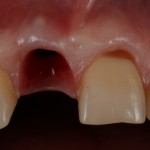

После удаления зуба и сопутствующей гранулемы, остается большая по размеру лунка с тонкой и поврежденной воспалительным процессом вестибулярной стенкой:

Первым делом, необходимо определиться с подготовкой лунки под имплантат. Проверить правильность позиционирования лунки можно с помощью аналогов имплантов, входящих в комплект XiVE Dentsply Implants:

Напомню, что при правильном позиционировании импланта в области фронтальных зубов, он прилегает к небной стенке лунки, а его ось выходит на небную поверхность будущей коронки. В крайнем случае, на режущий край.